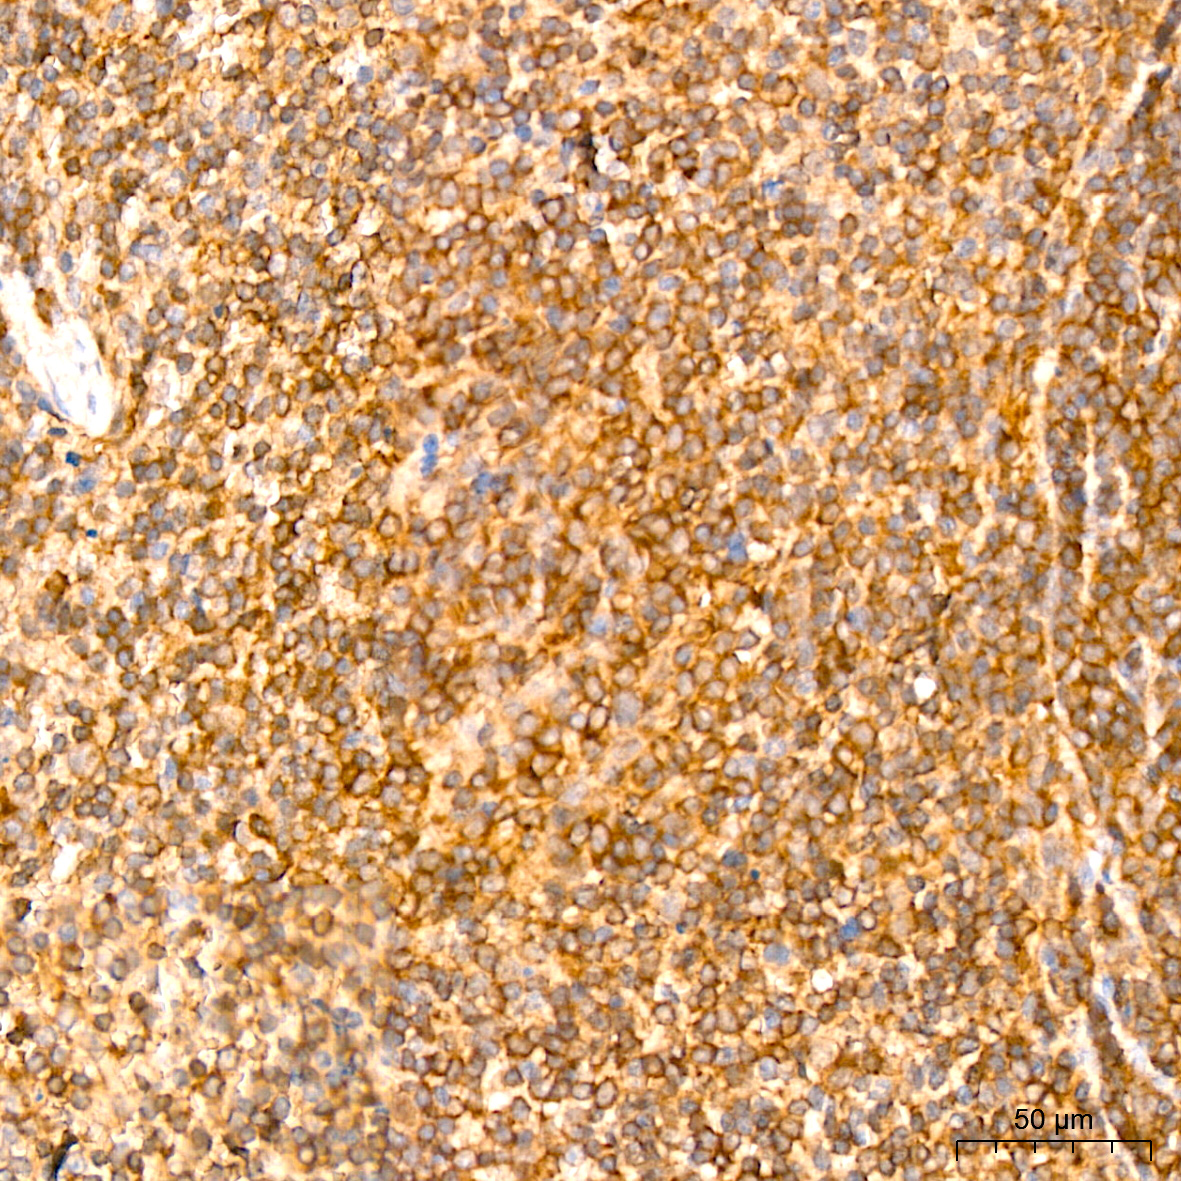

| Immunohistochemistry analysis of paraffin-embedded Mouse spleen tissue using NF-kB p65/RelA Rabbit mAb (A19653) at a dilution of 1:800 (40x lens). High pressure antigen retrieval performed with 0.01M Citrate Bufferr (pH 6.0) prior to IHC staining. |